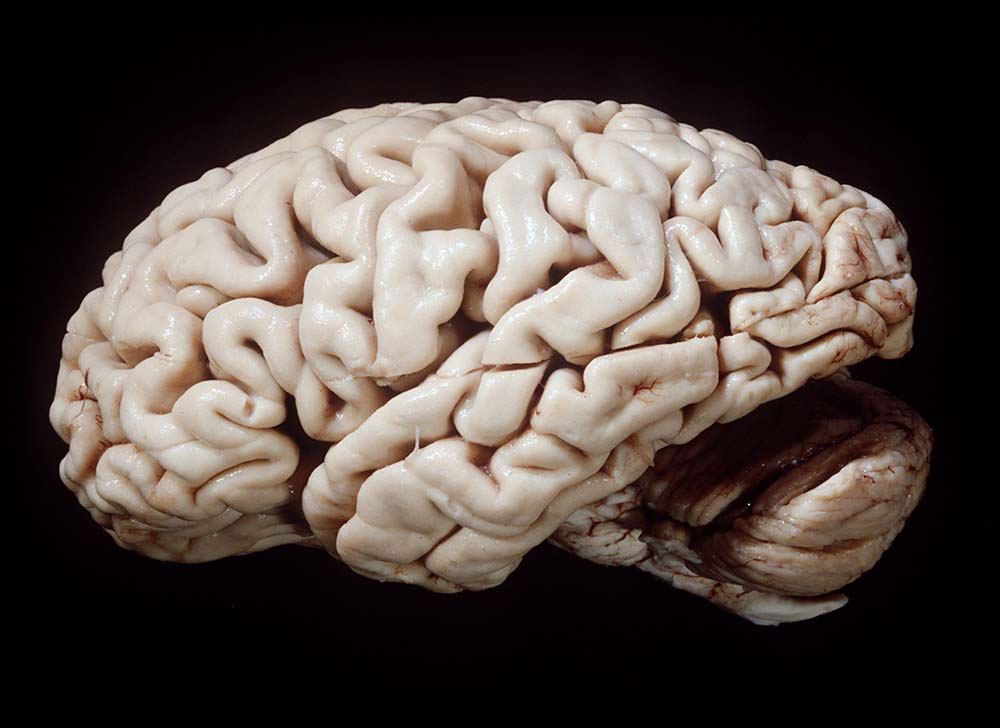

Normalbefund